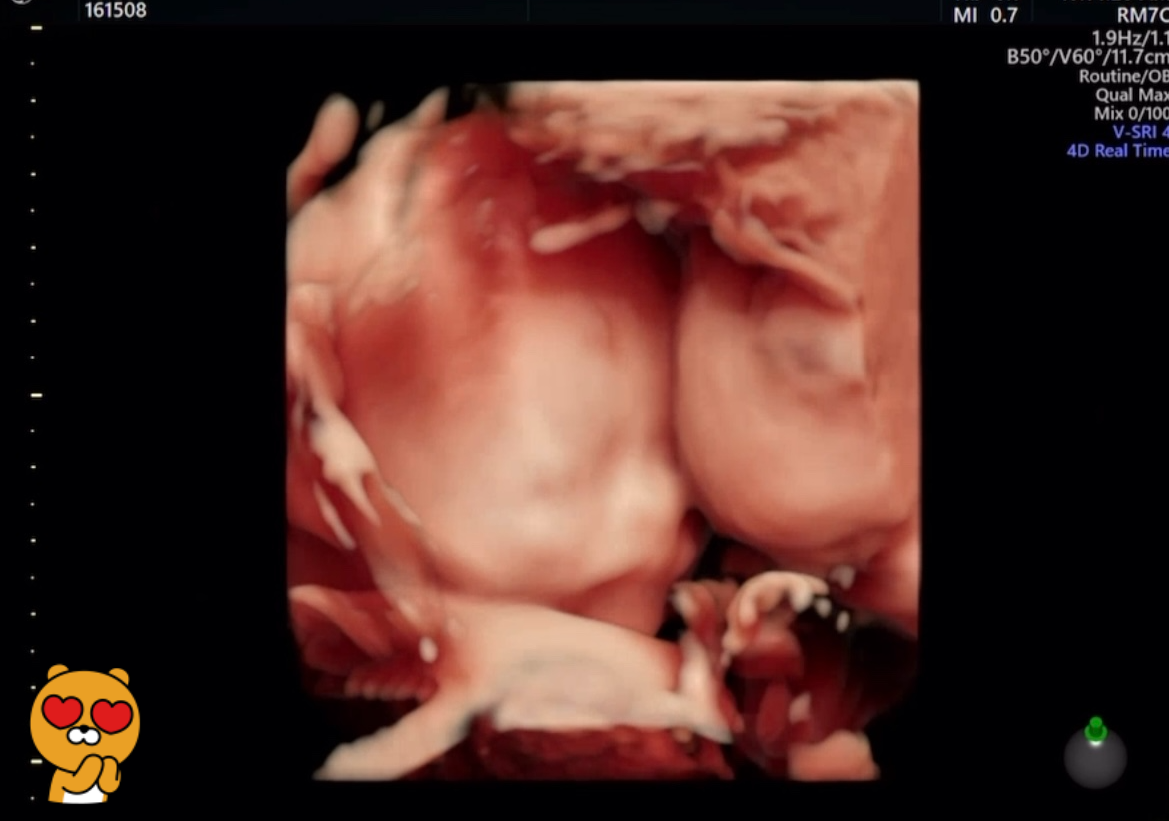

1년 전, 제주도로 태교여행을 다녀온 후, 설렘 가득 안고 23주차 정밀초음파를 보러 갔던 그날이요.

그날의 설렘과 긴장, 그리고 초음파 화면 속 축복이의 귀여운 몸짓들이 아직도 눈에 선해요.

장기나 신체에 이상은 없는지 꼼꼼히 살펴보는 정밀검사였는데,

축복이는 마치

“내가 잘 지내고 있으니까, 엄마 너무 걱정 마~”

하는 것처럼, 초음파 속에서 귀여운 장난을 시작했죠.

• 손가락을 보자 하면 주먹을 꽉!

• 얼굴을 보려 하면 손으로 얼굴 가리기!

• 심지어 다리까지 올려 얼굴을 쏙 숨기기!

초음파 봐주시는 선생님도 웃으시며

“짱구 같아요~”

라고 하셨을 정도였어요.